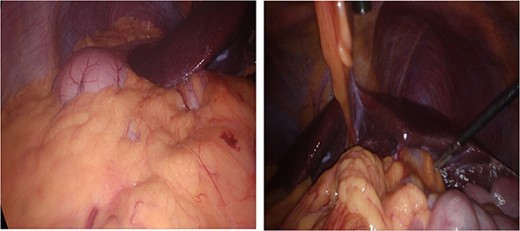

Anatomical variation with anatomical left lobe of the liver and fundus of the stomach in right upper quadrant (RUQ) and gallbladder in left upper quadrant (LUQ).

Dissection started with separation of omental adhesions from the fundus of the gallbladder. This was done using a combination of hook diathermy and blunt dissection techniques. Once these adhesions were taken down, Calot’s triangle was identified. Anatomical cross check was performed as usual by identifying segment IV of the liver, Hilar plate, and the hepatic pedicle. Dissection was kept lateral to the ‘line of safety’ and well above Rouviere’s sulcus. The operating surgeon used their right hand for the majority of dissection of Calot’s triangle as usual. Once Calot’s triangle was dissected, two structures were identified going into and out of the gallbladder, and Strasburg’s ‘critical view of safety’ (Fig. 4) was seen [4, 5]. The cystic duct and cystic artery were clipped with three 10 mm endoscopic haemostatic clips and ligated. The 10 mm ligaclipper was inserted through the subxiphoid port and placement of clips was controlled using the surgeon’s left hand. The gallbladder was then dissected from the gallbladder fossa and removed via the umbilical port in a Bert bag.